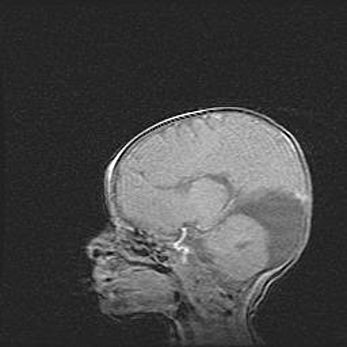

Подострая гематома правой гемисферы мозжечка.

Наружная гидроцефалия.

Возраст: 15 дней

Вес: 3100 г

Пол: женский

Окружность головы: 37 см

Срок гестации: 35-36 недель

При открытой наружной форме гидроцефалии у новорожденных расширяются и переполняются субарахноидные пространства.

Кровоизлияния в мозжечок имеют две клинико-анатомические формы: полушарные гематомы и кровоизлияния в червь.

К появлению этой патологии может привести: повреждения головного мозга, возникающие в результате асфиксии и гипоксии плода при беременности, или травмы во время родов. Редко гематома мозжечка может быть результатом первичной коагулопатии и сосудистой мальформации, диссеминированном внутрисосудистом свертывании, изоиммунной тромбоцитопении.